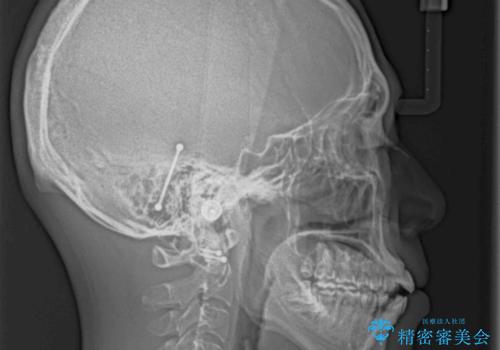

- 上下前歯の隙間と口元の出っ張った感じを気にして来院された患者様です。

上下の隙間は舌突出癖によるもので、またその癖により前歯が前方に出ている状態でした。

口元の出っ張りを改善するため、上下左右第一小臼歯4本を抜去し、ワイヤー装置にて矯正治療を行うこととしました。